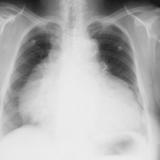

Pericardial "stripe"